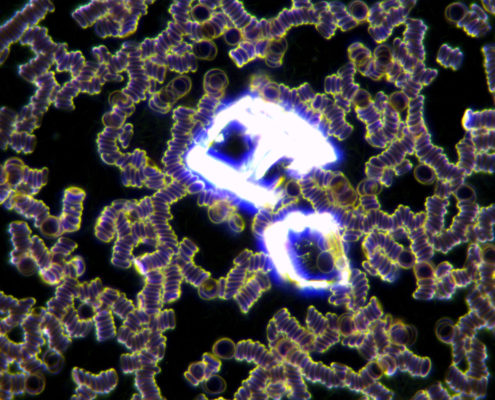

Darkfield analýza alebo aj analýza živej kvapky krvi v tmavom poli je mikroskopická technika, ktorá umožňuje screening komponentov krvi klienta v reálnom čase. Touto technikou je možné pozorovať javy, ktoré sa bežnými laboratórnymi metódami nezisťujú a preto je táto analýza vynikajúcim doplnkom k liečbe. Živú kvapku krvi je možné takto pozorovať len 10 – 20 minút.

Analýza je takmer bezbolestná, kvapka sa odoberie z prsta a dá sa na podložné sklíčko, zľahka sa prekryje krycím sklíčkom. Obraz krvi je snímaný kamerou do PC, čo umožňuje klientovi vidieť to isté čo vidí terapeut pod mikroskopom. Klient vidí jednotlivé krvinky a všetko čo sa v krvnej plazme deje v dostatočnej veľkosti. Výsledné zväčšenie je 1 000 – 2 000×. Pozorovaním kvapky krvi sledujeme prítomnosť, kvalitu a stav rôznych žiadúcich i nežiadúcich krvných zložiek, čo nám mnohé napovie o zdravotnom stave, aj keď nevedie k pomenovaniu presnej medicínskej diagnózy. Z každého pozorovania vytvárame fotografie, ktoré sú ukladané do karty klienta pre porovnanie pri následnej kontrole.

- prítomnosť cholesterolových kryštálov v krvi a zvýšené množstvo LDL cholesterolu, nedostatok omega 3 mastných kyselín